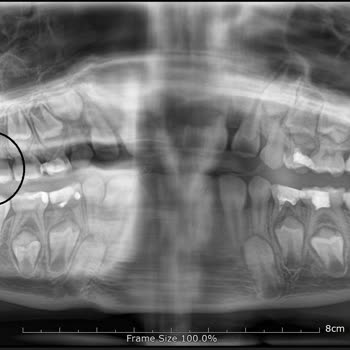

Hospident Fatih şubesinde 2 yılı aşkındır pedodontist d. Ml. İle dişlerimizin kontrol altına olduğunu düşünürken aslında pek de öyle olmadığını anladık. Şöyle ki, 8 yaşındaki çocuğunuzun kalıcı dişlerini korumak adına fissür işlemi yaptırmak için doktorunuz planlama yapıyor. Size başka işlemlerle il...